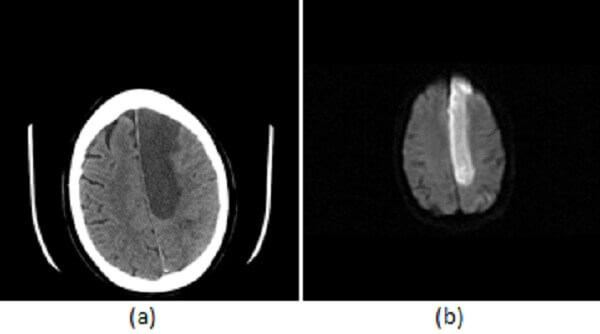

Diagnosis: Anterior cerebral artery territory infarct

Figure 1: (a) Noncontrast head CT demonstrates hypodensity and mass-effect involving the medial left frontoparietal lobes; (b) Increased restricted diffusion in this territory on DWI consistent with an acute infarct; and (c) MIP reconstructions from an MR angiogram demonstrate major segments of the anterior cerebral artery A1 (red arrow), A2 (blue arrow), A3 (green arrow).

ACA strokes are less common than those in other vascular territories, accounting for approximately 5% of ischemic strokes. Clinical symptoms of the ACA territory infarct include contralateral leg weakness with sparing of the face (as the ACA supplies the most medial (leg) portion of the sensory homunculus but not more lateral portions like the face). Frontal symptoms including abulia, transcortical motor aphasia (specifically a supplementary motor aphasia) and personality changes due to frontal lobe damage.